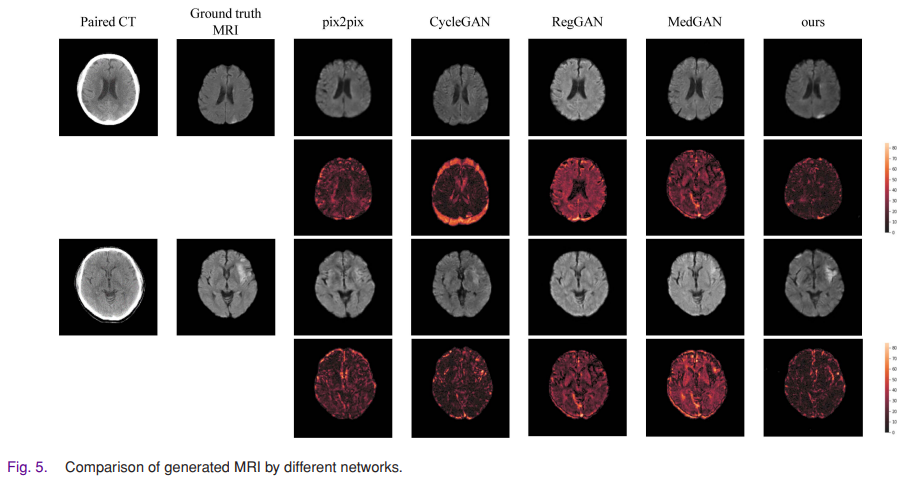

두 명의 숙련된 방사선 전문의의 주관적 평가와 평가지표를 사용한 결과, 생성된 MRI이미지가 실제 MRI이미지와 매우 유사한 것으로 나타났다.

또한 병변의 위치가 정확하고, 병변의 형태가 실제 병변과 유사해 의사들의 신속한 진단과 치료에 도움을 줄 수 있음을 확인했다.